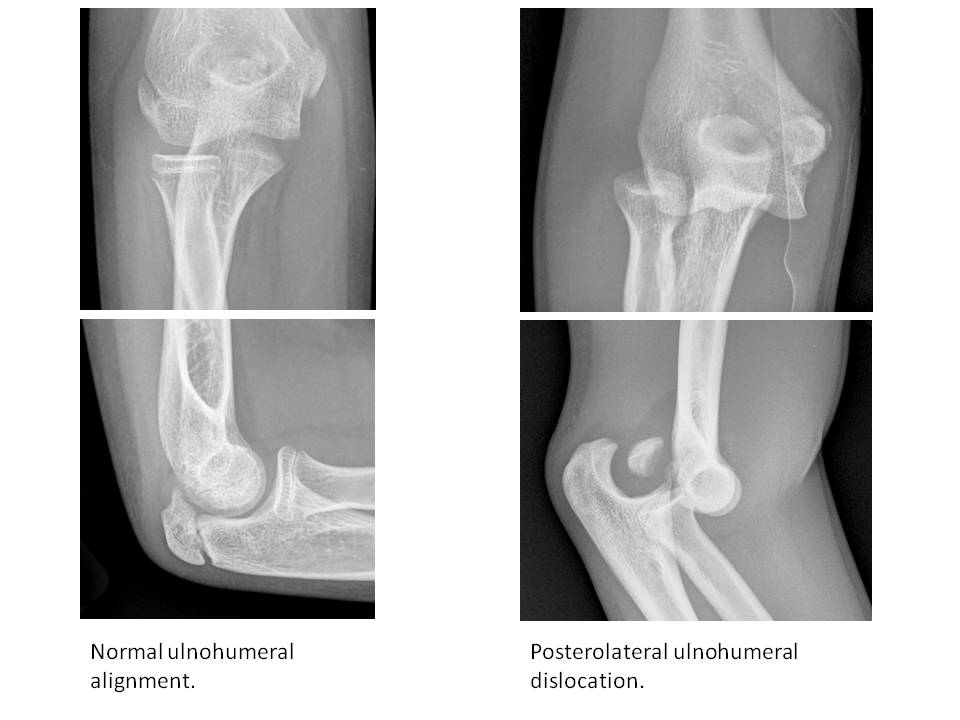

Alignment